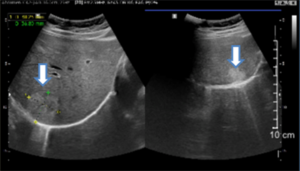

Case lâm sàng: Điều trị đích bệnh nhân ung thư biểu mô tế bào gan không còn chỉ định phẫu thuật tại trung tâm Y học hạt nhân và Ung bướuGS.TS. Mai Trọng Khoa, BSNT. Nguyễn Văn Tấn, BSNT. Đỗ Thị Thu Trang, PGS.TS. Phạm Cẩm Phương, TS. Phạm Văn Thái, ThS.BS....